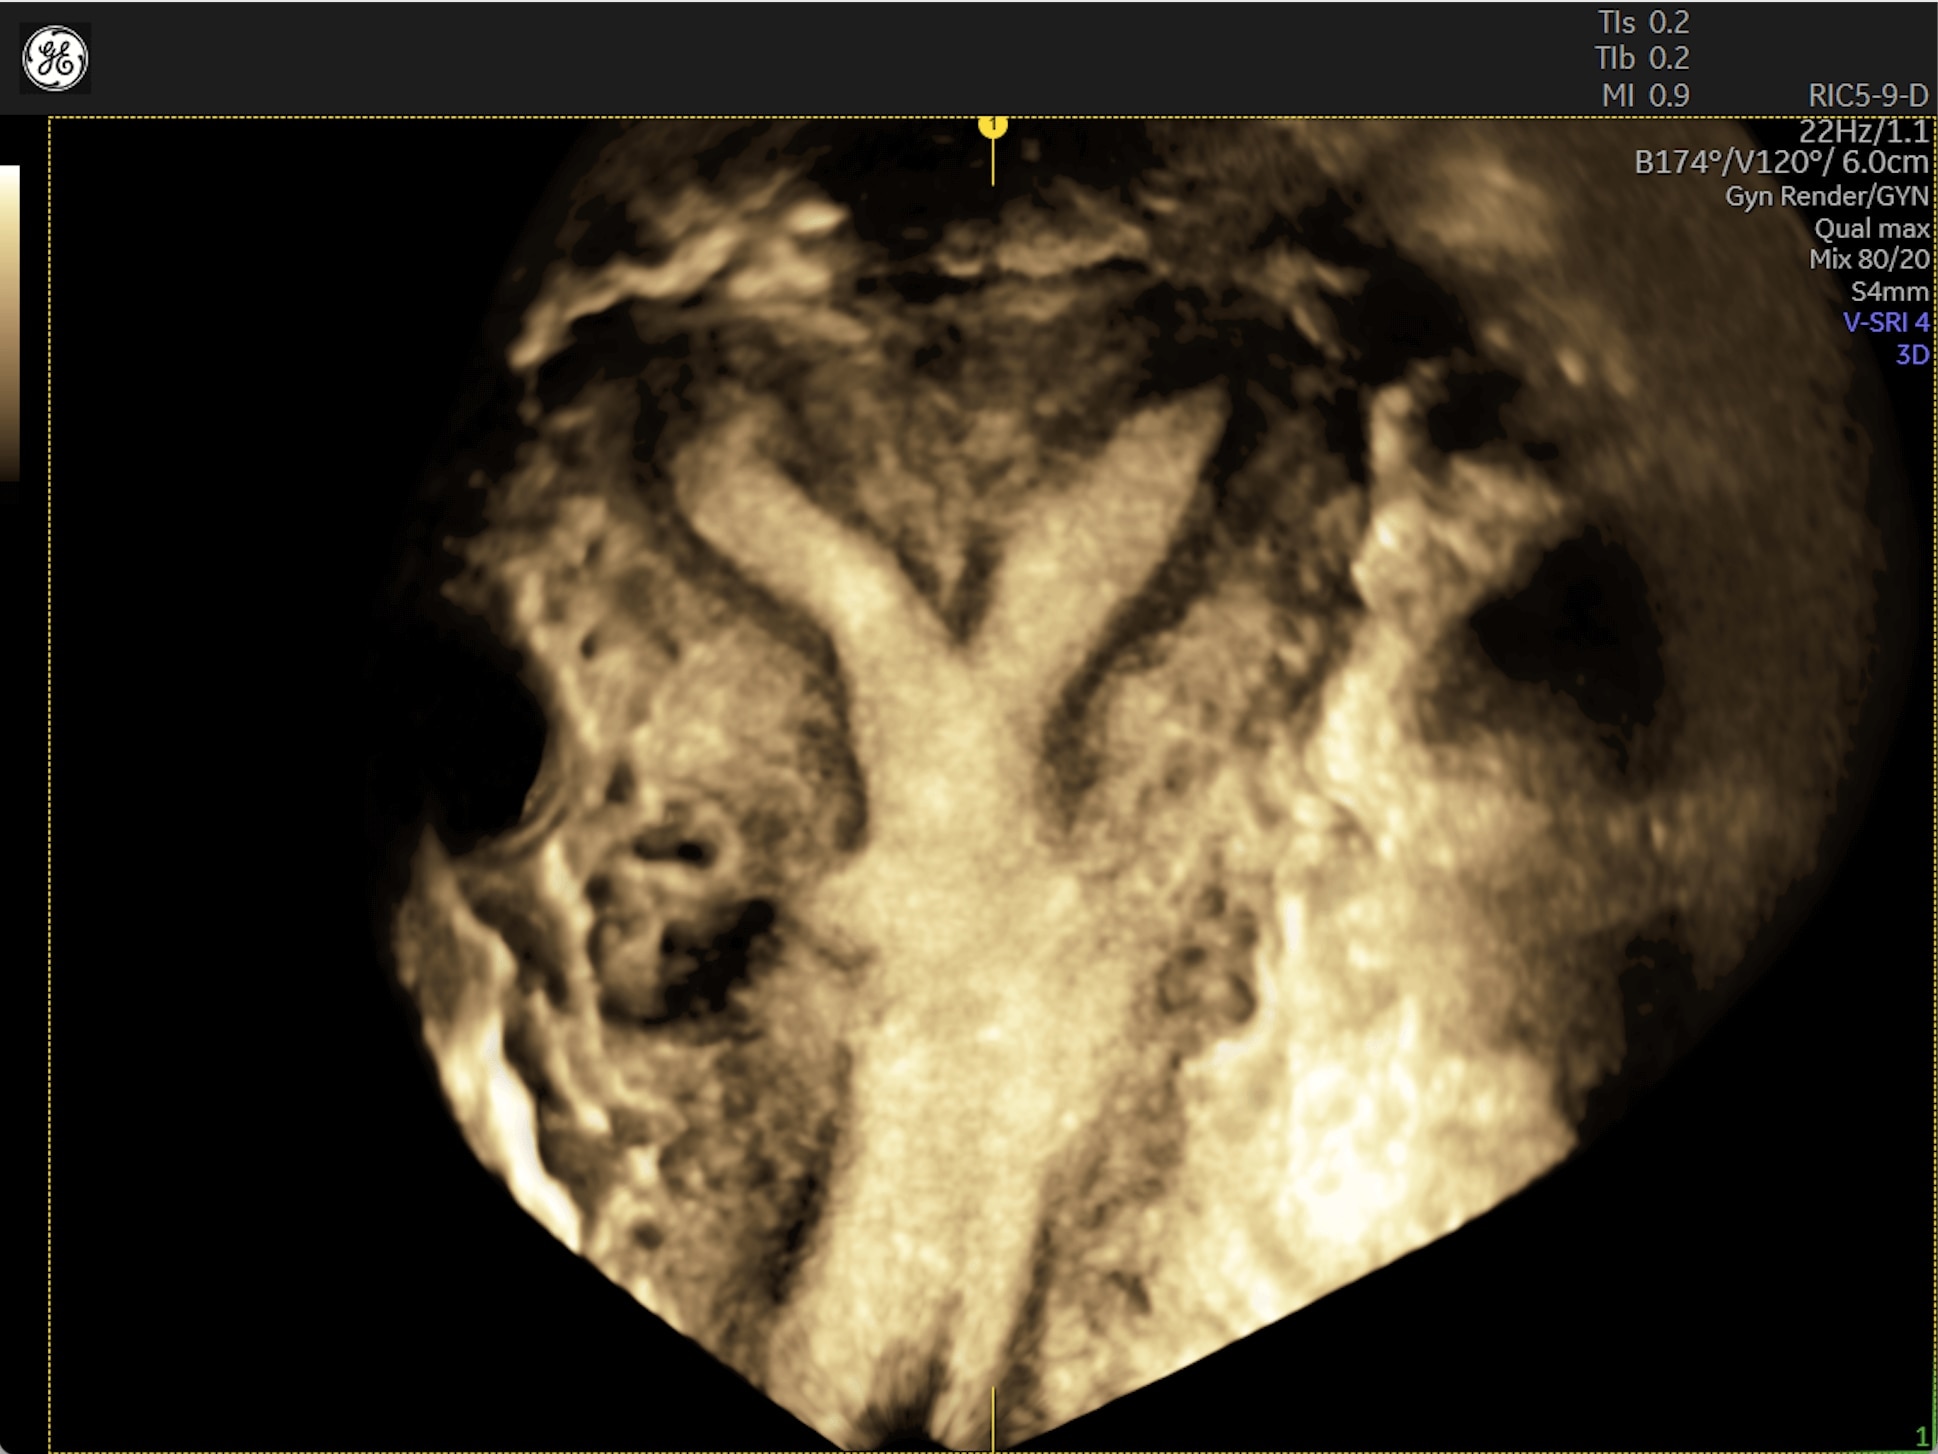

Generate spectacular 2D/3D and color Doppler images with increased penetration and stunning clarity, to help visualize critical details needed for diagnostic assurance. The Lyric Architecture unlocks new imaging and processing power to expand your imaging capabilities for years to come